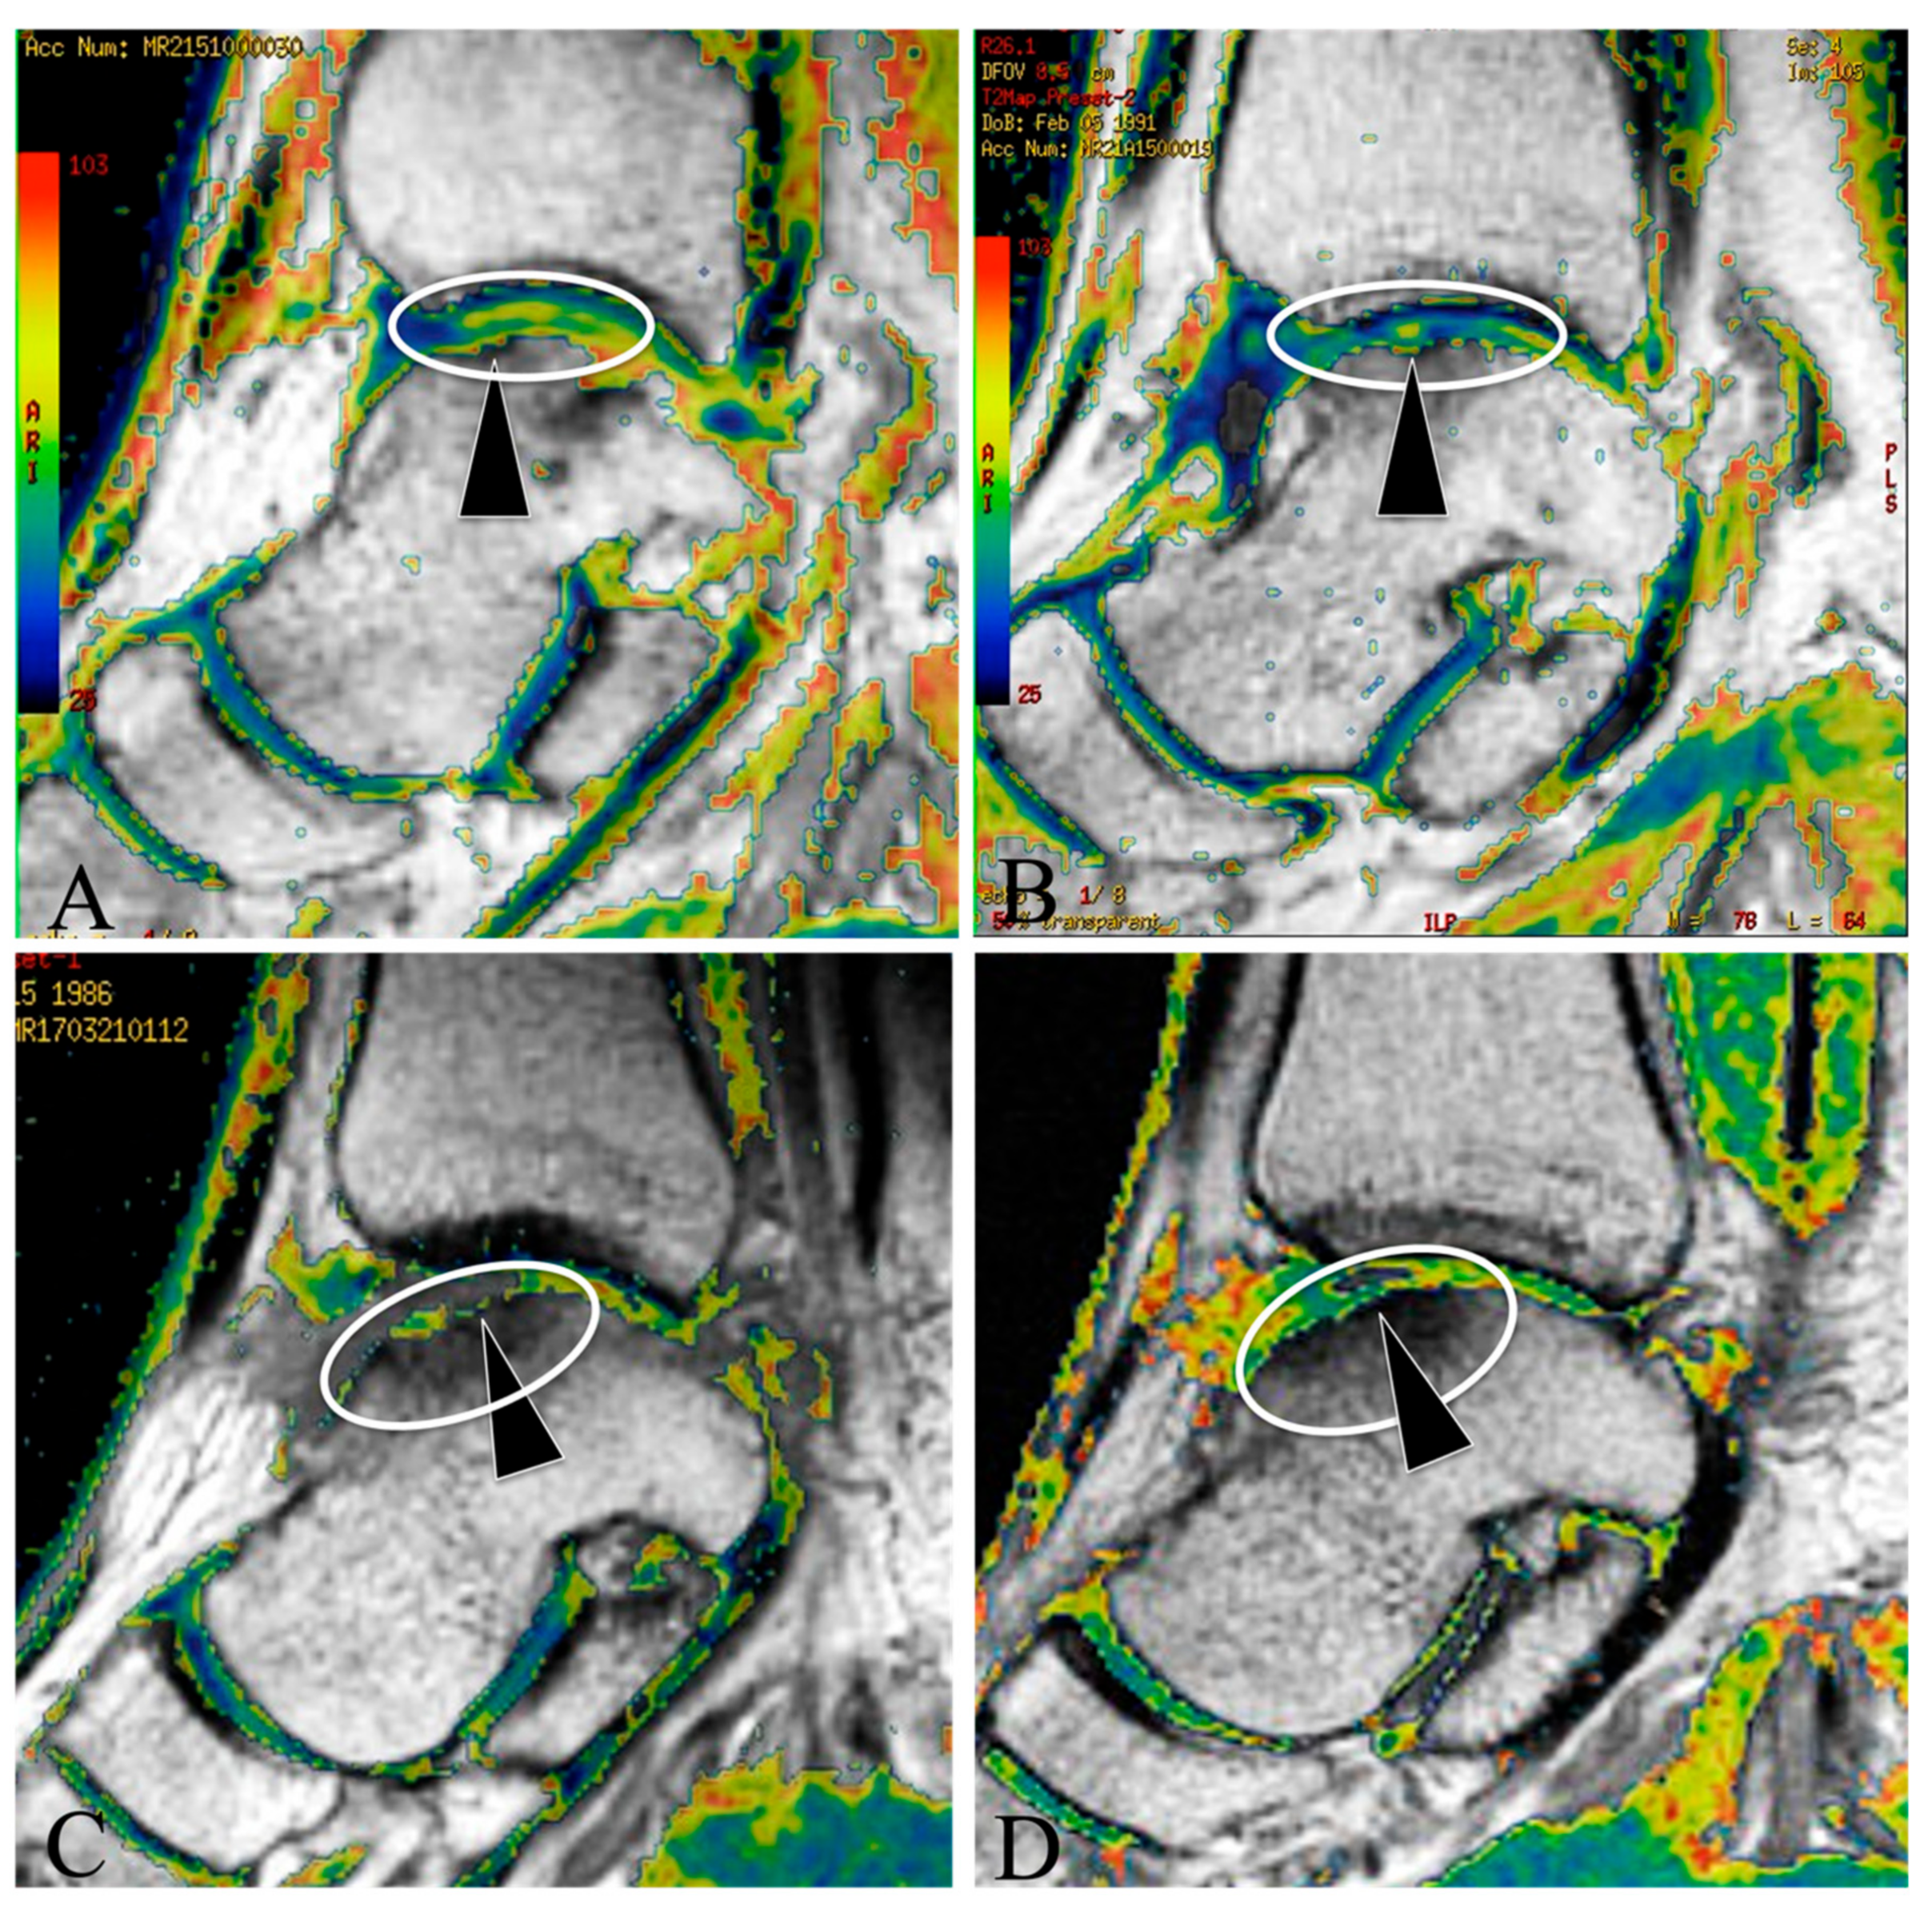

Baseline MRI T2 mapping for the patients showed evidence of OLT in both groups (Figure 2A,C), and the T2 mapping values of OLT areas did not have a significant difference between the MF + PRP and MF + ESWT groups at baseline (Table 3).

Figure 2.

MRI T2 mapping assessment on the cartilage quality in MF + ESWT and MF + PRP groups at baseline and 2y follow up (A) baseline T2 mapping for OLT patients in the MF + ESWT group, the ellipse showed an OLT area (yellow-green, high T2 mapping value), and the arrow showed an osteochondral lesion in a patient; (B) T2 mapping for the MF + ESWT group at 2y follow up, the ellipse showed the regenerated cartilage (blue-green, lower T2 mapping value) in the same OLT patient at 2y follow up, and the arrow showed the osteochondral lesion had been refilled with neo-cartilage tissue; (C) baseline T2 mapping for OLT patients in the MF + PRP group, the ellipse showed an OLT area (yellow, high T2 mapping value), and the arrow showed a cartilage defect in a patient; (D) T2 mapping for the MF + PRP group at 2y follow up, the ellipse showed immature regenerated cartilage (green-yellow, slightly lower T2 mapping value) in the same OLT patient at 2y follow up, and the arrow showed the osteochondral lesion had been refilled with immature neocartilage tissue.

At the 2y follow up, MRI T2 mapping showed a neo-regenerated cartilage tissue in all of the patients of the two groups (Figure 2B,D), however, it showed that some of the osteochondral lesion in the MF + PRP had been refilled with immature neocartilage tissue (with a green color) (Figure 2D), while the osteochondral lesion in the MF + MF + ESWT had been refilled with a relatively mature neocartilage tissue (with a blue-green color) (Figure 2B), and the T2 mapping value of the MF + ESWT group was lower than that of the MF + PRP group (Table 3).